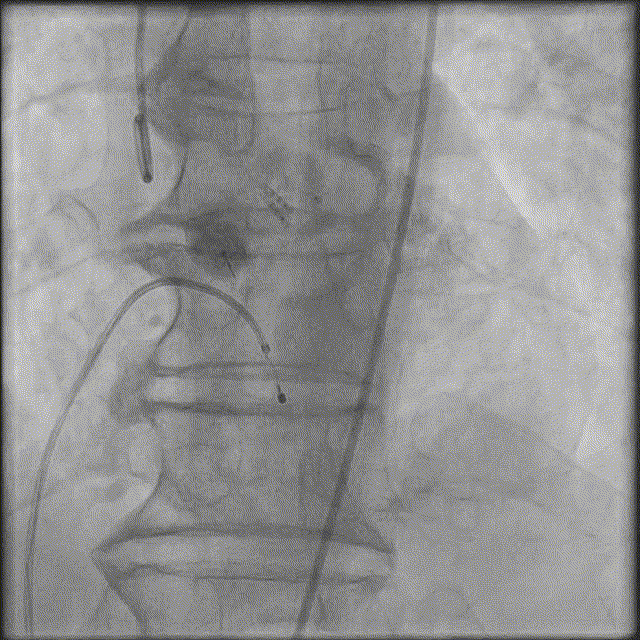

血管入路评估:

2. 超声引导精准穿刺右股主入路、左股副入路,及右股静脉;

3. 两把ProGlide预埋右股动脉,植入20F戈尔大鞘;

4. 右窦中心投照体位行主动脉根部造影;